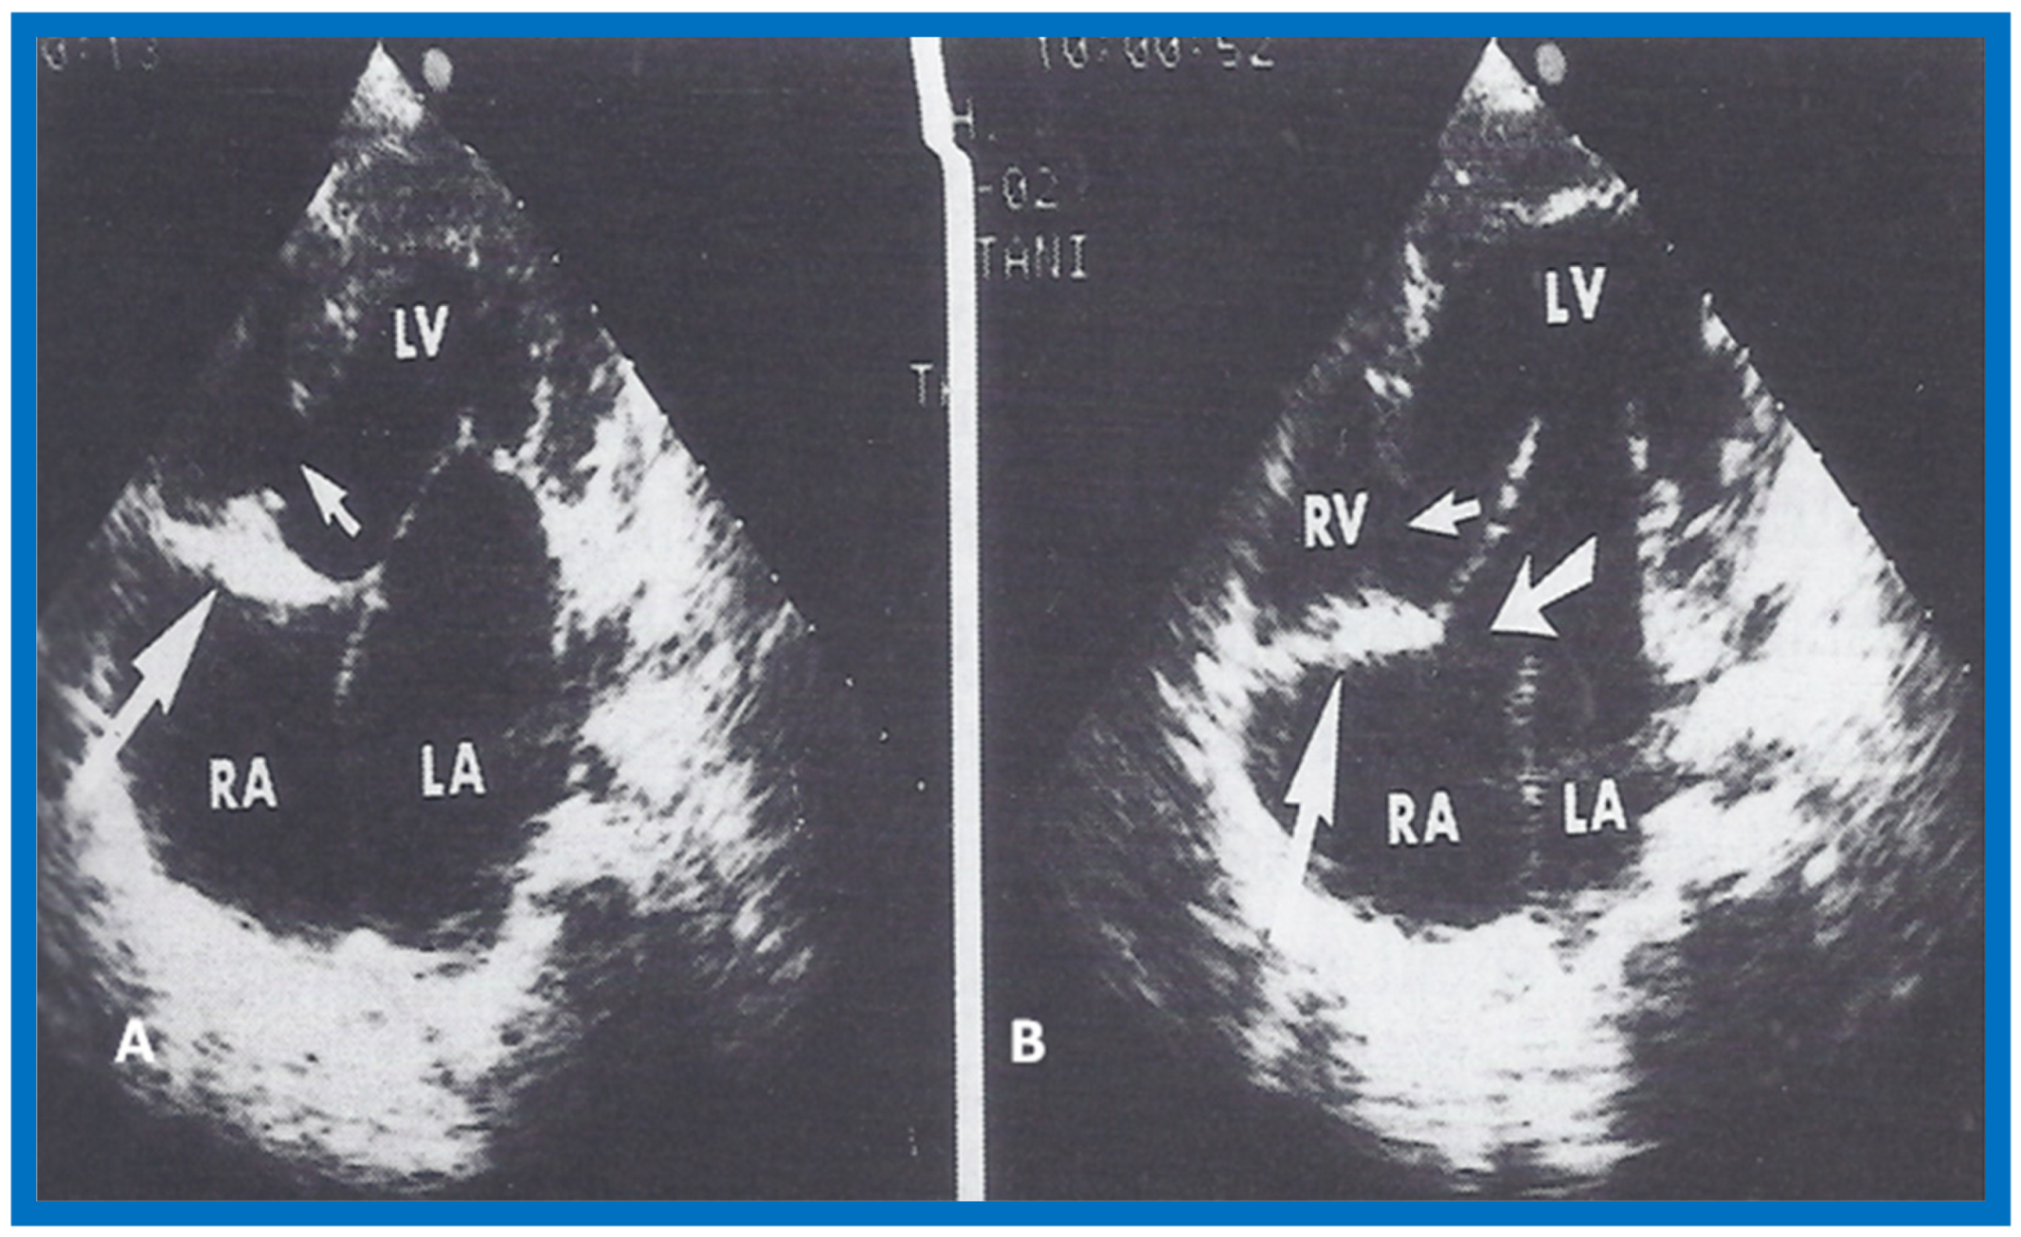

More recently, the author reviewed the echo-Doppler evaluation of tricuspid atresia [37,38,39]; these findings will be presented. M-mode echocardiography, while not diagnostic, is useful for evaluating the size of the left atrium (LA) and left ventricle (LV) and LV function. On 2D echocardiography, the atretic tricuspid valve is visualized directly as a dense band of echoes at the site where the tricuspid valve should be in the most frequent muscular type, as shown in Figure 14, Figure 15, Figure 16 and Figure 17. This anatomy is better demonstrated in apical and subcostal four-chamber views than in other views. The other types, namely membranous, valvular, Ebstein’s, atrioventricular septal and unguarded valve with muscular shelf (Figure 18) [40], are rare and may also be recognized on 2D echocardiography.

Following the demonstration of the atretic tricuspid valve, the sizes of the cardiac chambers were evaluated both by M-mode (Z scores) and 2D echocardiography; enlarged RA, LA and LV, and a small RV, were seen (Figure 14, Figure 15, Figure 16 and Figure 17). Pulsed (not shown) and color Doppler (Figure 19) studies were helpful in illustrating the right-to-left shunt across the patent foramen ovale or atrial septal defect. Contrast study using agitated saline with 2D imaging clearly demonstrated successive opacification of the RA, LA, LV and then the RV in that order, but such a study is not necessary for diagnosis.

Figure 19.

Selected video frame from subcostal view of a neonate with tricuspid atresia demonstrating right-to-left (R to L) shunt (arrow) across the interatrial communication. LA, Left atrium; RA, Right atrium. Reproduced from Rao P.S. [39].